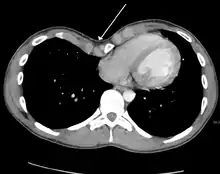

Many scales have been developed to determine the degree of deformity in the chest wall. Most of these are variants on the distance between the sternum and the spine. One such index is the Backer ratio which grades severity of deformity based on the ratio between the diameter of the vertebral body nearest to xiphosternal junction and the distance between the xiphosternal junction and the nearest vertebral body.[17] More recently the Haller index has been used based on CT scan measurements. An index over 3.25 is often defined as severe.[18] The Haller index is the ratio between the horizontal distance of the inside of the ribcage and the shortest distance between the vertebrae and sternum.[19]

Chest x-rays are also useful in the diagnosis. The chest x-ray in pectus excavatum can show an opacity in the right lung area that can be mistaken for an infiltrate (such as that seen with pneumonia).[20] Some studies also suggest that the Haller index can be calculated based on chest x-ray as opposed to CT scanning in individuals who have no limitation in their function.[21]

Pectus excavatum requires no corrective procedures in mild cases.[22] Treatment of severe cases can involve either invasive or non-invasive techniques or a combination of both. Before an operation proceeds several tests are usually performed. These include, but are not limited to, a CT scan, pulmonary function tests, and cardiology exams (such as auscultation and ECGs).[23] After a CT scan is taken, the Haller index is measured. The patient's Haller is calculated by obtaining the ratio of the transverse diameter (the horizontal distance of the inside of the ribcage) and the anteroposterior diameter (the shortest distance between the vertebrae and sternum).[24] A Haller Index of greater than 3.25 is generally considered severe, while normal chest has an index of 2.5.[19][25][26] The cardiopulmonary tests are used to determine the lung capacity and to check for heart murmurs.